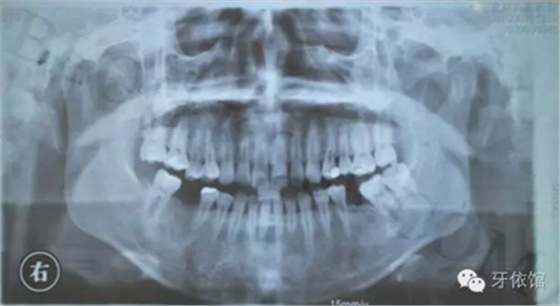

患者:女,28歲,此x光片為4年前拍的,左下6已于四年前行種植修復(fù),今天主要介紹右下6種植修復(fù)過程。計劃微創(chuàng)種植。

右下6口內(nèi)照片顯示牙槽嵴頂寬度并不是很充足,微創(chuàng)種植有一定的風(fēng)險,跟患者協(xié)商后,同意微創(chuàng)種植。